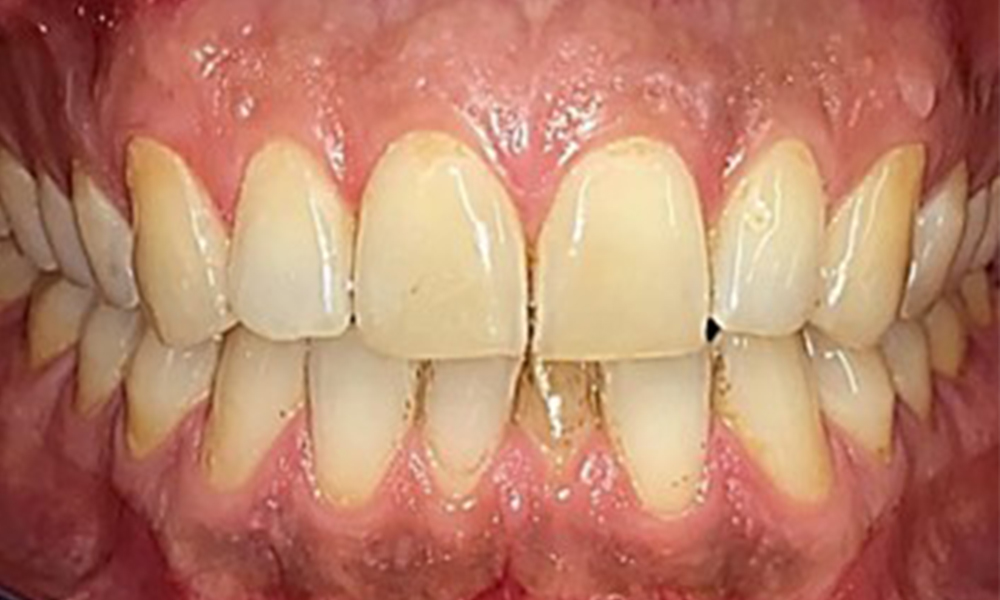

Frontal view

Fig. 2 Frontal view, © Dr R. Krapf

Extraoral and intraoral findings

There were no pathological extraoral findings. During intraoral examination, inspection of the frontal view revealed brownish discolouration near the keratinised gingiva and at the transition to the moveable mucosa (Fig. 2), which could be attributed to nicotine consumption. Whitish mucosal lesions were observed on the palate, particularly near the maxillary molar palatal surfaces, indicating increased keratinisation and can also be attributed to nicotine consumption. The tongue was covered with a removable white and brownish coating.